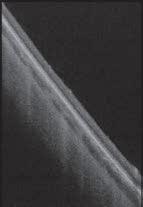

order to observe an individual mite in the clinical setting using a slit-lamp, the lash can be rotated at its base several times using tweezers, (termed the ‘Mastrota rotation’) until its tail emerges partially from the follicle. Another method is to exert ‘lateral tension’ on the lash to observe the emerging tail from the follicle opening without lash epilation.13

Lash epilation and in-vivo confocal microscopy are two research techniques used to count Demodex. In-vivo confocal microscopy involves applying the probe of the instrument to the eyelid margin. It provides complete observation of the lash contents, without the need to epilate the lash.10 In the lash epilation method, a lash with

cylindrical dandruff is epilated and observed under a microscope for the quantification of the mites attached to it. Both techniques are restricted to the research setting and are influenced by the lash chosen for observation, hence yielding variable results.14